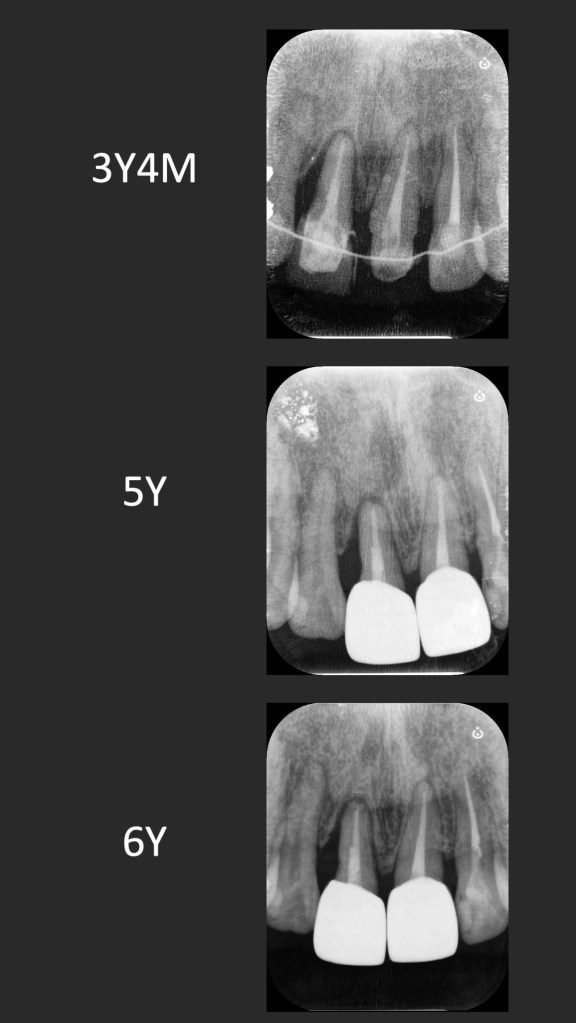

這個案例,最早沒把握能救回來,但是做完非手術治療,發現恢復非常好。

於是大膽地請矯正與假牙專科醫師一起幫忙完成。其實病人本身也同意,若途中狀況不好,還是得拔除。我知道這種案例,其實對其他專科來說,可能是有壓力的,不容易處理,也是難症。

好佳在,兩位神隊友都完成了,非常感謝合作專科的信任,還有,病患六年來維持得非常好,目前囊袋正常、零出血、零發炎。

回頭看,一開始就拔掉牙齒,改走其他路線,或許也可以,每位醫師選擇的或許不一樣,並沒有標準答案。

但是,能幫病患留下自己的牙齒,真的是很開心的一件事~~